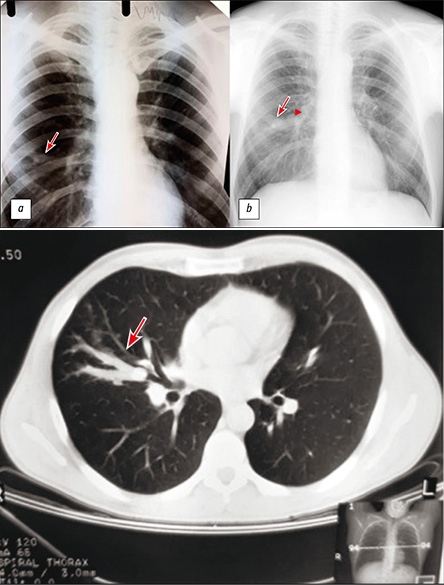

Long-term broncocele anamnesis, triggered by typical carcinoid

Abstract

The paper presents a case of a single bronchocele (bronchogenic retention cyst) caused by a typical carcinoid that was observed for a long time. During the initial complex examination, including computed tomography with intravenous contrast, fibrobronchoscopy, and immunological and bacteriological examinations of tuberculosis, there were no changes for the oncological and infectious nature. The changes were interpreted as the result of a postponed nonspecific inflammatory process. Most of them were monitored using chest X-ray and the changes were stable. After 15 years, a control chest X-ray revealed an increase in the size of the compaction in the lung and the appearance of a mass with calcification in the medial sections of the compaction zone. Additional examination, including computed tomography with biopsy, determined that the obstruction of the bronchus was caused by a neoplasm [according to histological examination (typical carcinoid)].

It should be noted that the initial detection of negative study results requires oncological alertness and periodic examinations in dynamics.